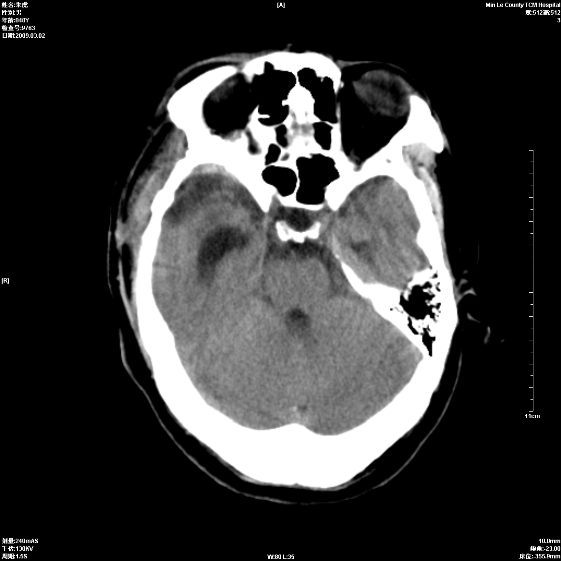

标题: CT18444:男颅咽瘤术后一月复查脑积水增多 [打印本页]

标题: CT18444:男颅咽瘤术后一月复查脑积水增多

右侧额叶局软化灶,梗阻性脑积水。

右额叶软化灶。梗阻性脑积水。

手术后改变

1、右额叶脑软化

2、脑积水

四脑室上方积水,右额叶软化灶。

1)右侧额颞部颅骨术后改变。2)右侧额颞叶脑软化灶。3)脑积水(梗阻性)。

手术后改变1、右额叶脑软化2、梗阻性脑积水。